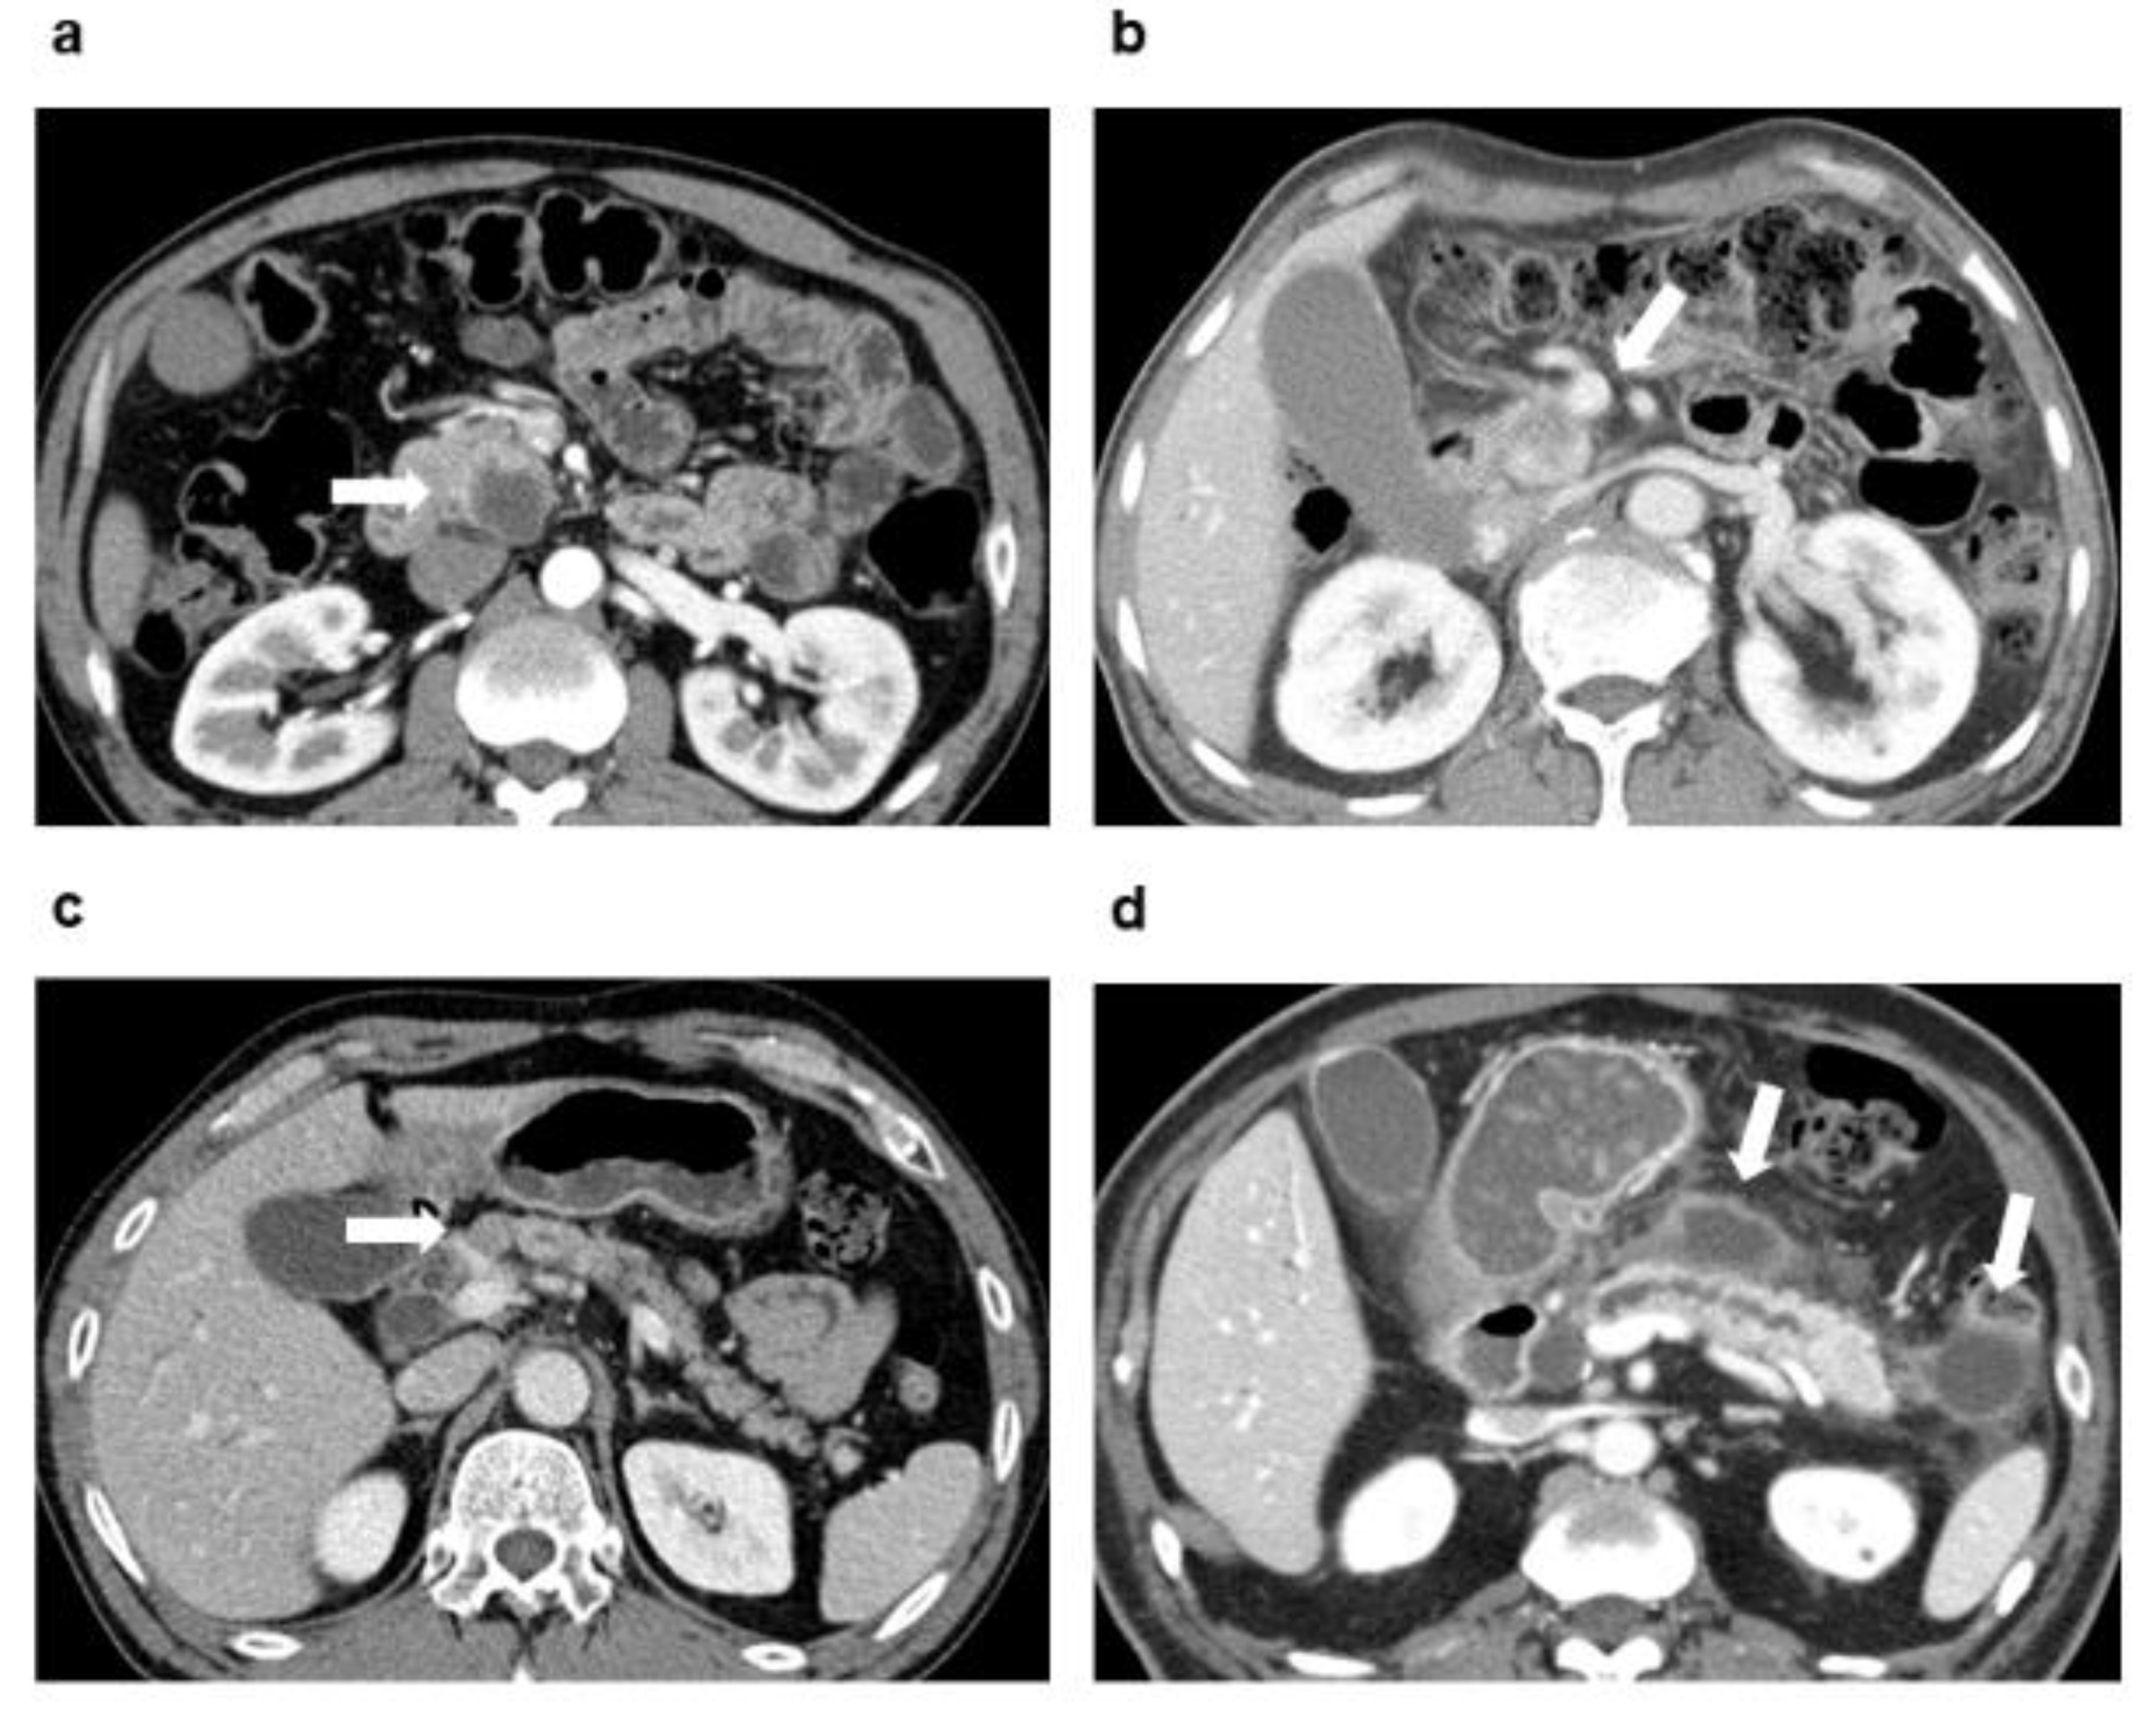

2.2. CT Imaging

2.3. Image Analysis

| Necrosis on CT | 1.64 | 0.97–2.79 | 0.066 | 2.42 | 1.39–4.21 | 0.002 |

| Associated pancreatitis or pseudocyst on CT | 0.51 | 0.30–0.86 | 0.013 | 0.54 | 0.30–0.98 | 0.041 |